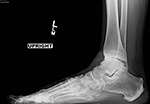

Our standing xray protocol is used to determine the overall shape, structure and integrity of the ankle and foot, while facilitating a comparison with the opposite side. The x-rays also assist in the evaluation of associated conditions.